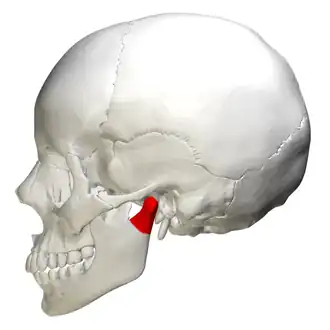

Position of condyloid process (shown in red). | |

The condyloid process or condylar process is the process on the human and other mammalian species' mandibles that ends in a condyle, the mandibular condyle. It is thicker than the coronoid process of the mandible and consists of two portions: the condyle and the constricted portion which supports it, the neck.

Position of condyloid process (shown in red)

Position of condyloid process (shown in red) -